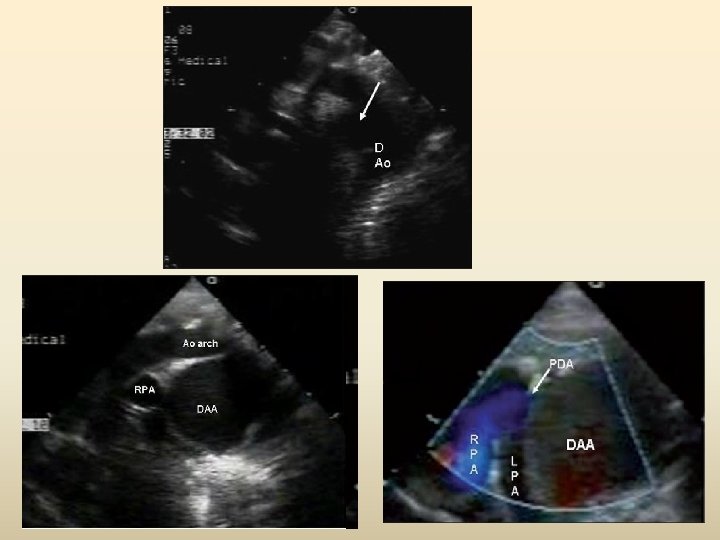

Ductal aneurysm • ~8% • May present at any age • In adults may present as a thoracic mass or with cardiovocal syndrome • In children may spontaneously resolve • Requires surgical excision / covered stent placement